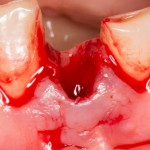

А вот и сама лунка:

Лунка кровоточит — и это нормально. Кровотечение — это защитная реакция организма. Я бы больше переживал из-за его отсутствия, чем из-за сильного кровотечения.